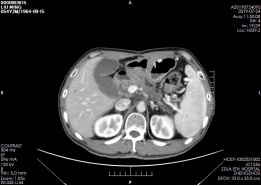

刘某术后来院复诊,1月复查CT肿瘤灭活(图2),3月复查CT肿瘤消除(图3),6月复查CT未见复发及转移(图4),1年复查CT部分胰腺组织萎缩、纤维化,肿瘤未见复发及转移(图5),2年复查CT(图6),病情稳定,未见肿瘤复发及转移。

▲ 图五 术后1年CT 部分胰腺组织萎缩、纤维化,肿瘤无复发及转移

▲ 图六 术后2年CT 病情稳定,肿瘤无复发及转移